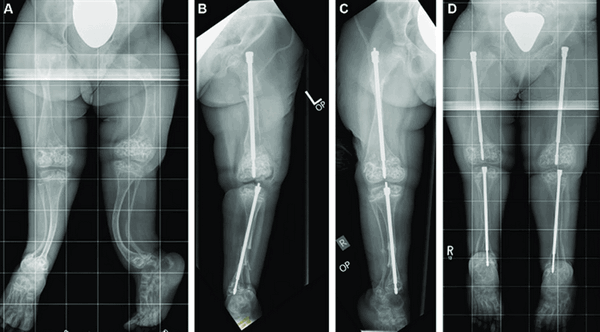

При переломах необходима тщательная репозиция костных отломков и гипсовая иммобилизация. При выраженных деформациях костей показано проведение хирургического лечения - корригирующей остеотомии с интрамедуллярным или накостным остеосинтезом.

При выраженной деформации костей проводят корригирующую остеотомию, которая помогает исправлять форму, размер конечностей. Во время хирургического лечения пораженная кость рассекается, исправляется ее форма и далее она фиксируется специальными конструкциями, то есть проводят остеосинтез.

Он бывает двух видов: накостный и интрамедуллярный. В первом случае фиксирующая конструкция находится в теле больного, но снаружи кости. Во втором случае изделие полностью зафиксировано внутри кости.